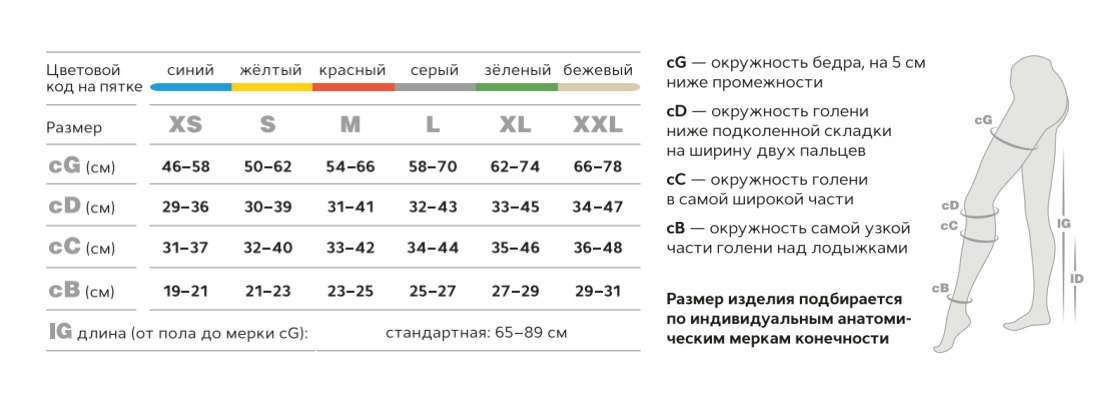

—цветовая индикация пятки соответствует определенному размеру;